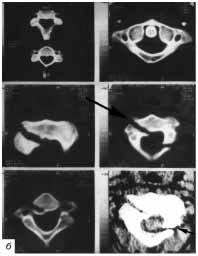

Рис. 6. Перелом С2 позвонка: а - на боковой рентгенограмме

шейного отдела позвоночника с поворотом в 3/4 выявляется двойной

контур дужки С2 позвонка (указан стрелкой). Из-за выраженного болевого

синдрома рентгенограммы выполнялись в жестком гол овод ержателе;

б - при КТ шейного отдела позвоночника у этого же больного обнаружен

косой перелом тела С2 позвонка и его дужки слева (линия перелома

указана стрелкой). Диастаз между отломками составил 7 мм.

При проведении же КТ-исследования удается выявить перелом позвонка с

достаточно большим диастазом костных отломков (рис. 6 а, б). Отсюда и

тактика лечения больного будет иной.